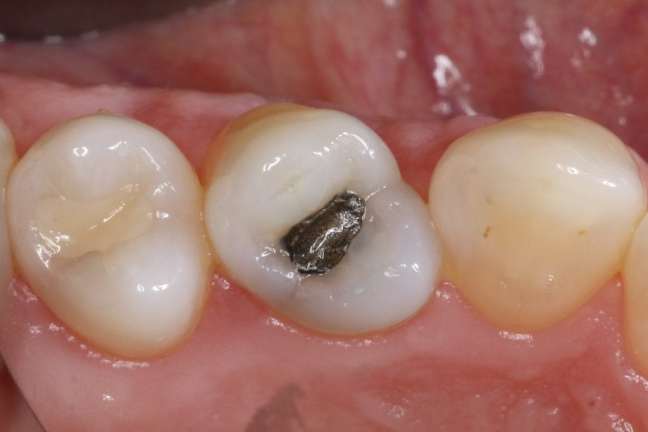

Az amalgám tömés veszélyes? El lehet távolítani biztonságosan is?

Az amalgám tömésről sokat vitáznak, mivel higanyt is tartalmaz, ami nagy mennyiségben mérgező lehet. Itt van egy összefoglaló a legfontosabb tudnivalókról:Veszélyes az amalgám tömés?Igen is, meg nem is. Az amalgám tömés kb. 50%-ban elemi higanyt tartalmaz, de szilárd formában kötődik más fémekhez (ezüst, réz, ón), így stabilnak számít.A legtöbb embernél nem okoz problémát, és a … Az amalgám tömés veszélyes? El lehet távolítani biztonságosan is? részletei...